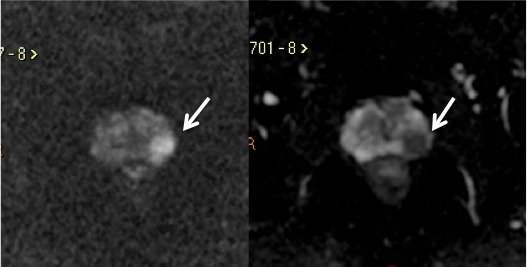

A Difusão (DWI - Diffusion weighted imaging) estuda o movimento randômico das moléculas de água nos tecidos, estimando indiretamente a densidade celular e a viabilidade das membranas celulares. A sequência gera múltiplos conjuntos de imagens, de acordo com o número de fatores de difusão ou “valores de b” escolhidos. O aparelho também gera um mapa de coeficiente de difusão aparente (ADC – apparent diffusion coefficient), que é um conjunto de imagens que permite a quantificação das propriedades de difusão. Desta forma, uma lesão com difusibilidade restrita aparece como uma área hiperintensa no DWI, e com redução da intensidade de sinal no mapa ADC.11

A restrição à difusão das moléculas de água no câncer de próstata é atribuída ao aumento da celularidade das lesões malignas, com redução do espaço extracelular, e consequente restrição à livre movimentação das moléculas de água. Portanto, a DWI tem o potencial de diferenciar lesões benignas de malignas, sendo fundamental na detecção do câncer de próstata.13,19(fig. 7).

Figura 7. Mesmo paciente da figura 4, imagem ponderada em Difusão (A) e o mapa de ADC (B) mostram lesão na zona periférica esquerda com restrição à difusão das moléculas de água, caracterizado por hipersinal no DWI e baixo sinal no mapa de ADC.

Em uma metanálise recente, a DWI isolada apresentou sensibilidade de 62% e especificidade de 90% no diagnóstico do câncer de próstata. A sensibilidade é maior quanto maior o volume tumoral e o escore de Gleason. É importante ainda ressaltar que a sensibilidade da difusão para a detecção do câncer de próstata é muito maior na zona periférica, em torno de 79%.19A DWI é limitada na avaliação da glândula central, já que nódulos de hiperplasia prostática podem apresentar restrição variável à difusão. Para tumores da glândula central, as imagens ponderadas em T2 parecem ter melhor capacidade de detecção do câncer do que a difusão.14

Estudos têm demonstrado ainda que os valores de ADC têm forte correlação com a agressividade tumoral, sendo que tumores com escore de Gleason maior apresentam valores de ADC mais baixos. Portanto, além do diagnóstico, a Difusão pode fornecer informações relativas ao prognóstico.11